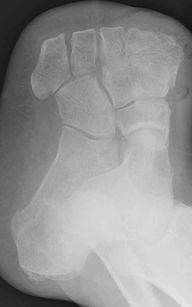

Similarly, feet consist of twelve bones (excluding the bones of the toes which are not important here) tied together with sinews and ligaments. It is easy to drive a nail between the bones without hurting any of these bones. Indeed, there are two famous "surgical lines" in foot amputation where you can take off part of the foot without damaging any of the bones. The x-ray image to the left shows a foot after amputation of the toes and part of the ray bones. One can clearly see the gap between the two heel bones (in the center of the image) which would be a suitable place to drive through a large nail. Hence, the spike merely separated the bones as it passed through the flesh.